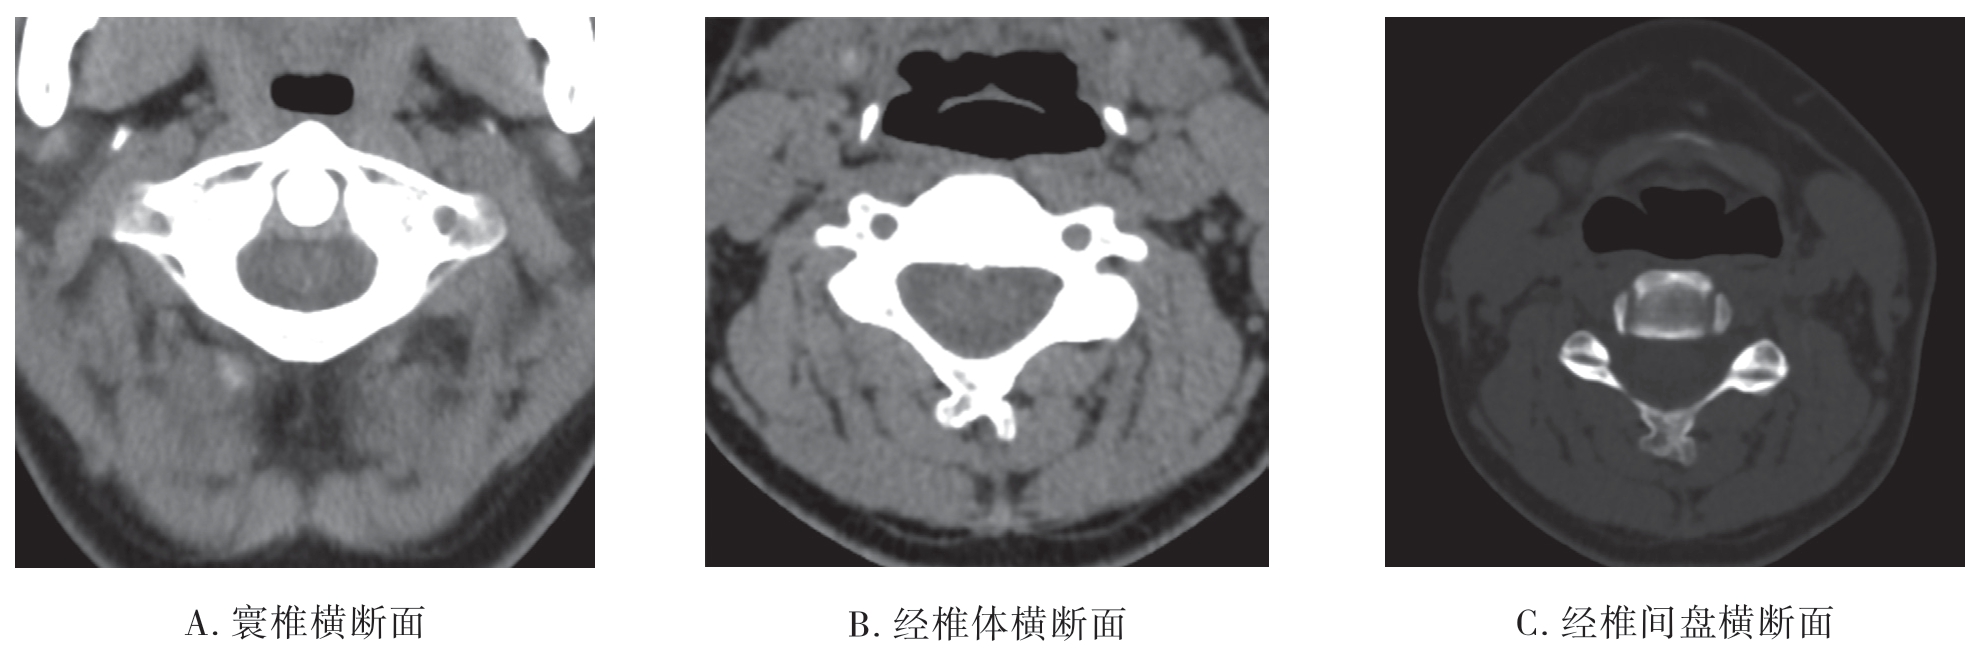

(1)颈椎CT平扫

1)寰椎CT平扫:寰椎横断面可显示寰椎前结节、前弓、侧块、横突、后弓、横突孔,枢椎齿状突,茎突(图7-2-5A)。

2)下颈椎CT平扫:经椎体中部平面横断面可显示椎体、椎弓根、椎板组成的骨性椎管,椎管内可见硬脊膜囊、脊髓、硬脊膜外腔、椎体后缘的后纵韧带、附着于椎弓板内侧的黄韧带、横突及横突孔、棘突等结构。经颈椎椎间盘平面可显示椎动脉、上下关节突、椎间关节、椎板、脊髓、钩突、钩椎关节(图7-2-5B、C)。

图7-2-5 颈椎CT平扫